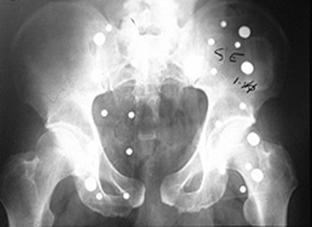

TRAUMATISMELE PELVIENE

Banda de stabilizare Dallas Fractura de bazin. Radiografie in

incidenta AP

Fractura de bazin

. Radiografie in incidenta AP Fractura de spina